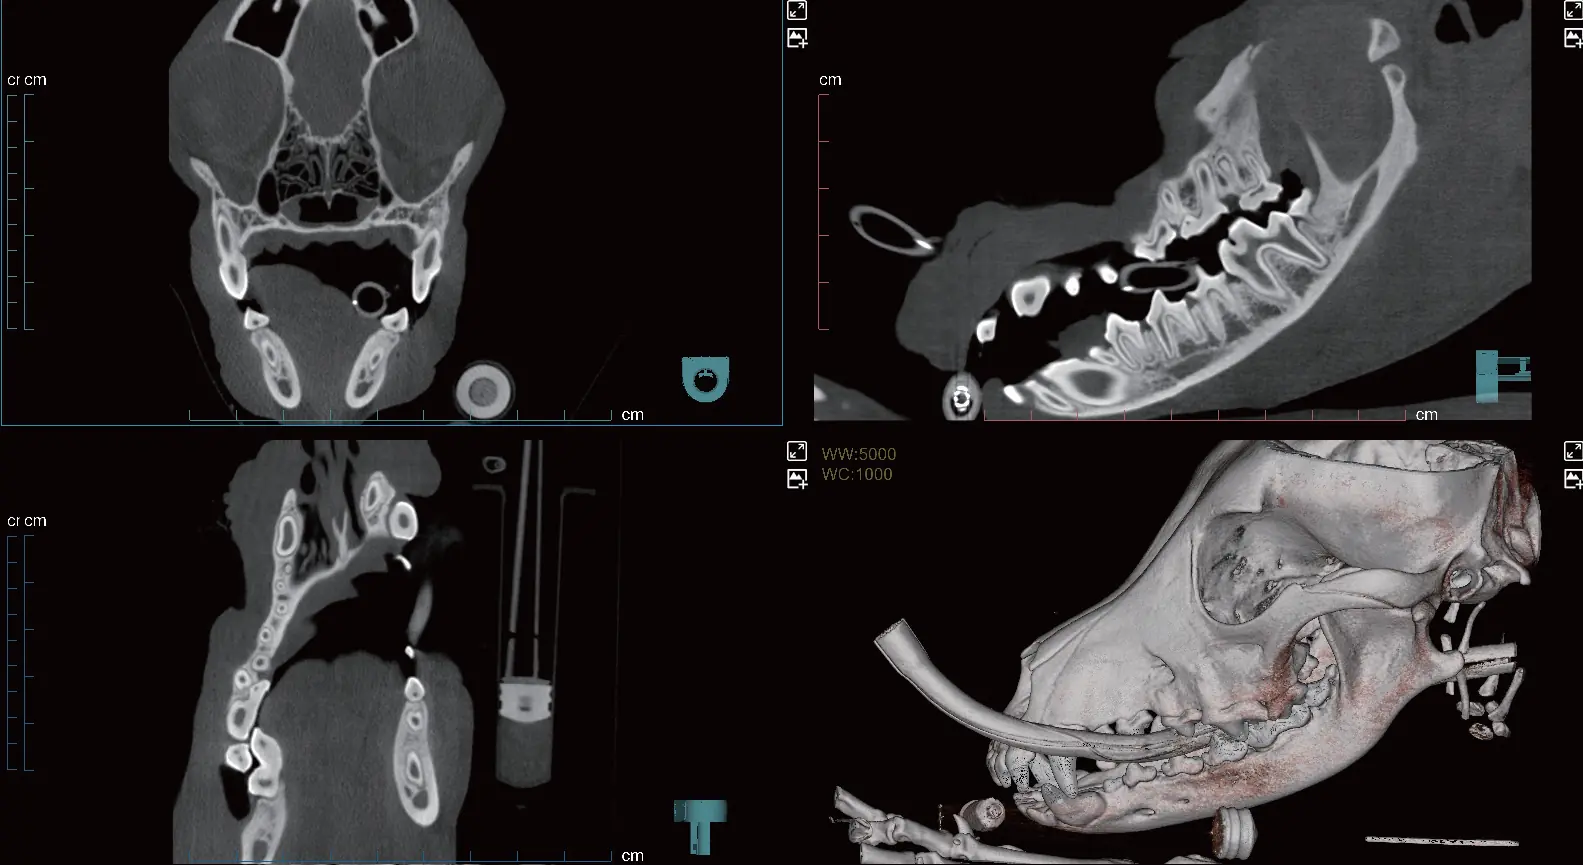

PANAROMİK

Tam Ark ve Çene için Tek Tarama

Yüksek çözünürlüklü dental görüntüler sunar; akıllı artefakt düzeltme sayesinde pulpa boşluğu ve periodontal ligament gibi ince yapılar net bir şekilde görüntülenir.